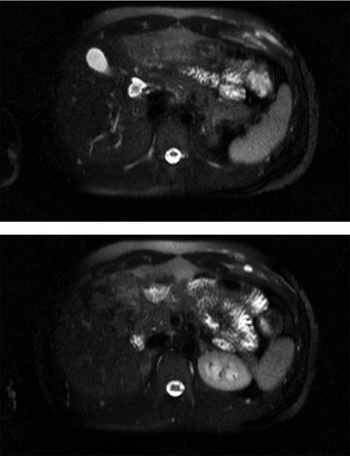

Figure 3: MRI post contrast – small intramuscular fluid collection that demonstrates rim enhancement. There is diffuse periosteal enhancement of the sixth rib. The appearance is suggestive of infectious process with an intramuscular abscess and associated osteomyelitis anterior rib

Figure 3: MRI post contrast – small intramuscular fluid collection that demonstrates rim enhancement. There is diffuse periosteal enhancement of the sixth rib. The appearance is suggestive of infectious process with an intramuscular abscess and associated osteomyelitis anterior rib(click to enlarge)

Work up for endocarditis and abscess elsewhere was unremarkable. An ultrasound-guided needle aspiration of the swelling was inconclusive. An MRI thorax was arranged and showed periosteal enhancement of the sixth anterior rib, suggestive of infectious process (osteomyelitis) with an intramuscular abscess (Figure 3). The findings were reconfirmed by a whole body isotope scan with no other hot spot (Figure 4). The patient was treated for osteomyelitis for six weeks as per hospital guidelines. The patient responded clinically and biochemically.